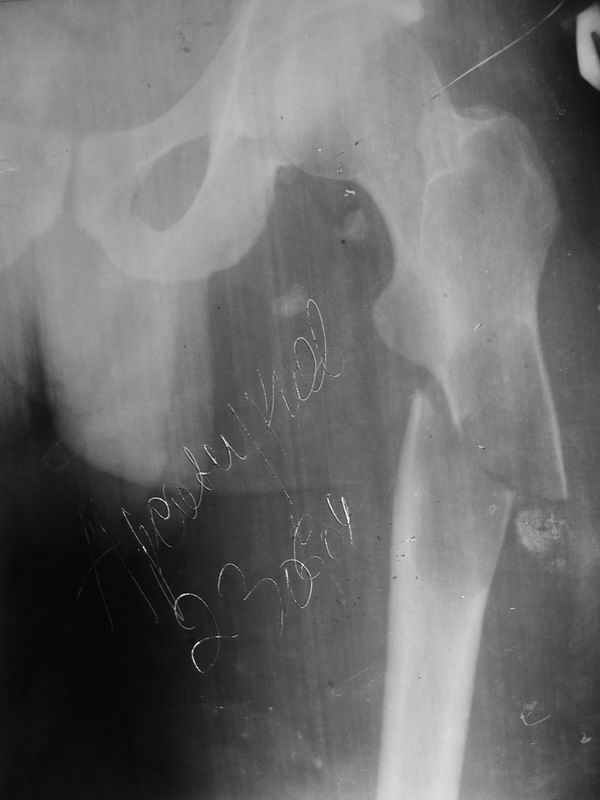

Добрый день, уважаемые коллеги! Мои коллеги из Грозного просили проконсультировать случай больного М. 26 лет. Боли беспокоили около 1 года в области подвздошной ости слева,

по поводу чего неоднократно обледовался - неоднократно выполнены снимки тазобедренного сустава. Снимки бедра не выполнялись. 1,5 месяца назад, находясь на работе, поднимаясь по лестнице в больнице почувствовал сильную боль, упал. При этом произошел перелом верхней трети бедра. На рентенограммах, представленных во вложении обнаружен патологический перелом. Траматологи расценивают это как кистозную дисплазию, хотя уверенности нет. Сейчас находится на склетном вытяжении. Каков прогноз заболевания? Верна ли тактика, показаны ли в будущем какие-то вмешательства? Заранее спасибо. С наилучшими пожеланиями, Бекхан.